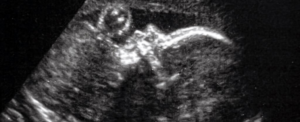

Лікарі вперше в світі провели операцію на мозку плода в утробі матері

Вперше хірурги успішно виправили серйозну ваду розвитку мозку плода.

Керуючись ультразвуком, хірурги з дитячої лікарні Бостона та жіночої лікарні Бригама в США застосували хірургічну техніку під назвою емболізація для лікування рідкісного передпологового стану. Судинна аномалія, яка називається мальформацією вени Галена, дозволяє крові текти небезпечно швидко через частину мозку після народження дитини. Успіх процедури дає нову надію на лікування захворювання до того, як зросте ризик ускладнень.

Тому Орбах і його колеги проводять клінічні випробування, щоб оцінити можливість лікування захворювання до народження. Їхній пацієнт був плодом на терміні вагітності 34 тижні та 2 дні (повний термін становить близько 40 тижнів), і вони використовували ультразвук, щоб контролювати їх під час виконання процедури емболізації.